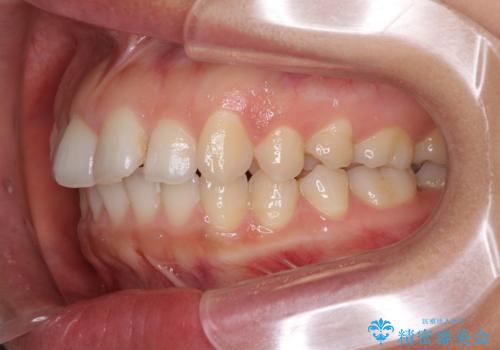

インビザライン矯正で前歯のデコボコを改善

- 前歯のデコボコを気にして来院された患者様です。

目立たないことを最優先にしたいとのことで、デコボコは軽度であったことから、インビザラインにて矯正治療を行うこととしました。

骨格的に下顎骨が左にずれており、上下の正中一致は困難ではありましたが、IPR(歯と歯の間を削る)や後方への移動など組み合わせて、できる限り改善しました。

インビザラインはマウスピースを外している時間が長いと、長期間使用しても前歯のデコボコはあまり改善されません。こちらの患者様は治療期間が長くなり、装着時間が短くなってしまったことで、気になる部分の改善により長期間を要するようになってしまいました。